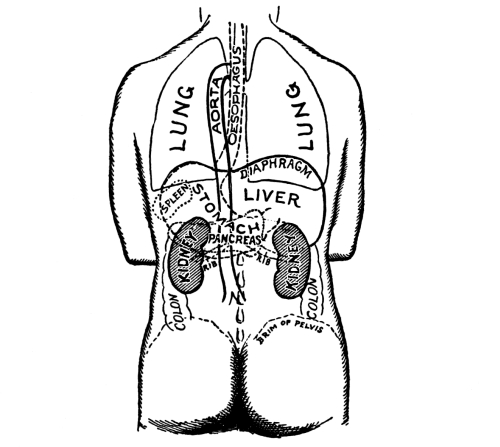

The Abdominal Cavity, 132—Muscles of the Abdomen, 132—The Peritoneum, 134—Abdominal Regions, 134—Salivary Digestion, 136—The Pharynx, 139—The Esophagus, 138—The Stomach, 138—Gastric Digestion, 139—Vomiting, 140—Intestinal Canal, 141—The Small Intestine, 142—Intestinal Digestion, 143—Absorption in Intestine, 144—The Large Intestine, 145—Food and Metabolism, 147—The Liver, 149—The Gall-bladder, 152—The Pancreas, 153—The Spleen, 153—The Suprarenal Capsules, 154—The Kidneys, 155—The Urine, 156—The Ureters, 159—The Bladder and Urethra, 159. |